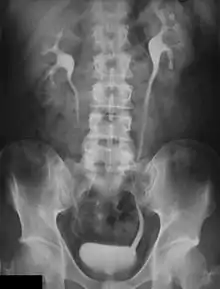

Urografía

La urografía es un examen radiográfico de contraste, que consiste en la realización de radiografías seriadas para ilustrar el paso de contraste previamente administrado por vía intravenosa.[1] El contraste permite la exploración y el estudio de diversas secciones de las vías urinarias y detectar alteraciones en la secreción urinaria, desde el parénquima renal hasta la vejiga.

El estudio se basa en visualizar la excreción renal con el paso de los medios de contraste yodados que logran oscurecer la orina y, por tanto, hacer visibles las cavidades naturales de las vías urinarias: los conductos colectores del riñón, uréter y vejiga urinaria. La urografía permite la exploración morfológica y funcional de estos .

Después de inyectar un medio de contraste a base de yodo en la vena, la urografía permite ver y estudiar las diferentes secciones del tránsito de excreción de la orina: cálices y ampolla renales, los uréteres y la vejiga.[1] De cada una de estas secciones se evaluará el tipo, la ubicación, el tamaño, el curso (en el caso de los uréteres) y la apriencia de las paredes tubulares. Además de estos hallazgos morfológicos, se pueden demostrar hallazgos funcionales, tales como apariencia, la durabilidad y la simetría de la eliminación, la intensidad y homogeneidad de la opacidad y la motilidad de las diversas secciones (la pelvis renal, uréteres y vejiga).

Una encuesta realizada correctamente debe permitir la exploración y el estudio de los riñones, cálices renales, uréteres y vejiga. Este último debe ser considerado cuando complete el llenado y, posteriormente, después de la micción del contraste. En la sospecha de la ptosis renal, debe ejecutarse una radiografía en posición vertical, lo que permite una documentación más precisa sobre la localización del riñón.